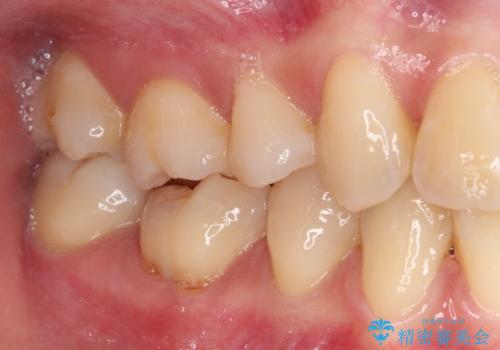

- 奥歯が食事中に歯が欠けて、しみて痛いとのことで来院された患者様です。

レントゲン写真からも、舌側に大きな虫歯があることが分かりました。

症状から神経を取り除く可能性も考慮し、オールセラミッククラウンにて補綴治療することとしました。